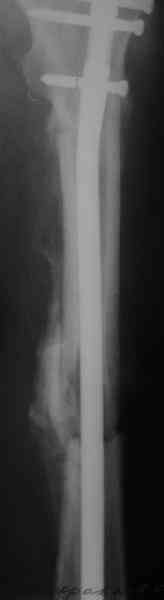

Саша, последний штифт, пожалуй, перегнули?

> Саша, последний штифт, пожалуй перегнули?

Там заход сделан как для прямого штифта, не через вертел.

И правда, не через вертел. Тогда зачем гнули?